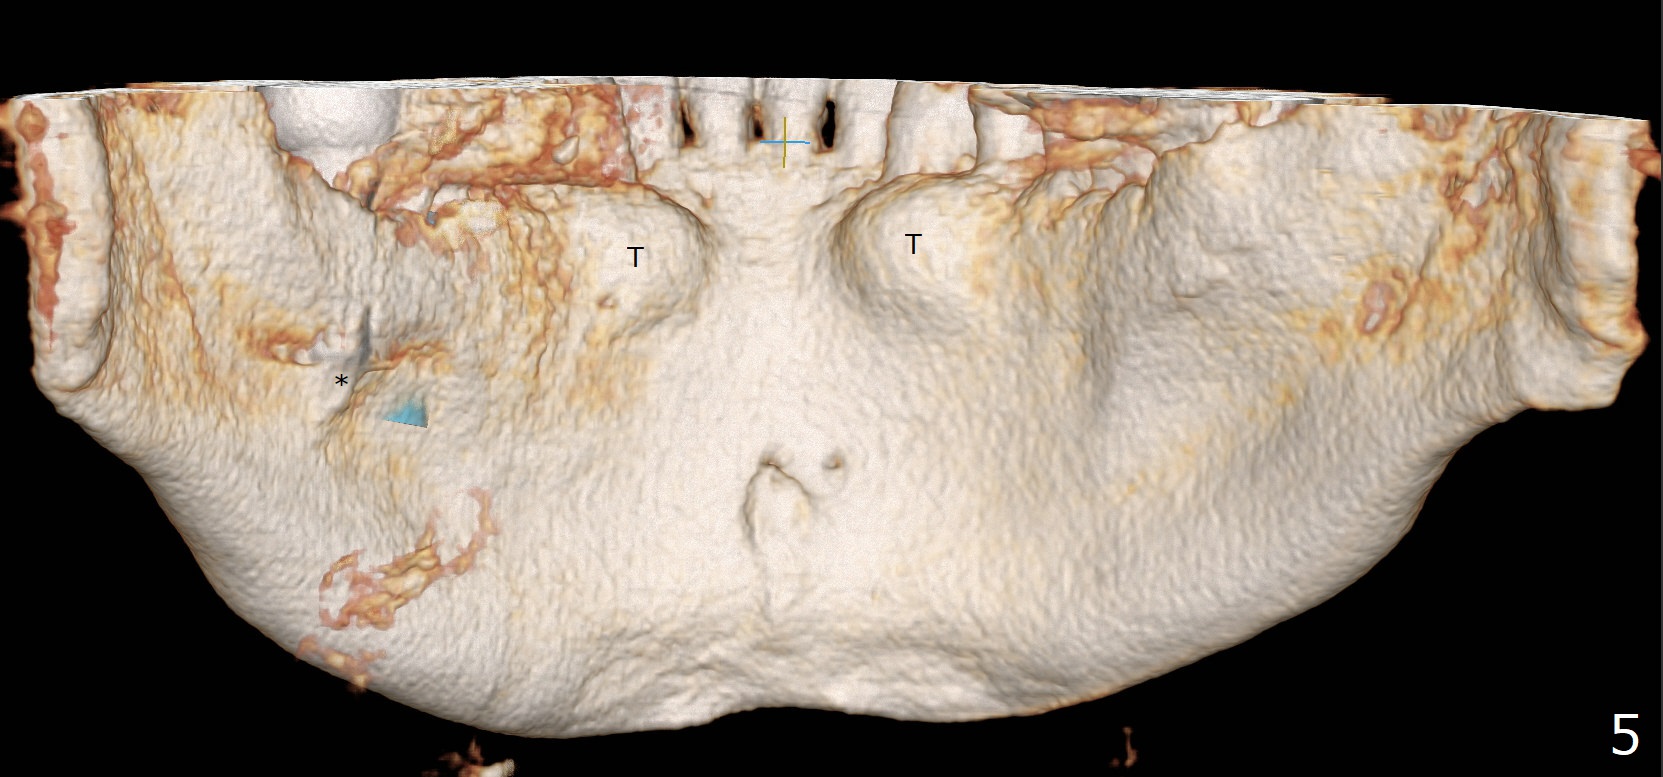

Submandibular Fossa

Fig.5 is a lingual view of the mandible (CT 3-D image).  T: torus; *: #31 implant sticking into the submandibular fossa.